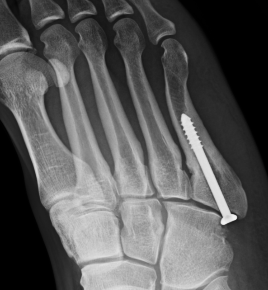

Screw fixation Zone 2 nonunion

Screw fixation Zone 3 nonunion

Entry point

- 5th metatarsal is not straight

- high and medial to get straight shot

- avoids plantar insertion peroneus brevis

- screw diameter 3.5 / 4.5 / 5.5 / 6.5

- screw threads must be distal to fracture site to allow compression